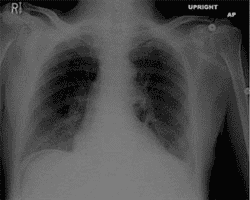

51) A 62-year-old man presents to the emergency department (ED) with one hour of severe epigastric pain. He has been having some epigastric pain exacerbated by eating for the last several days. He feels nauseous, and has vomited once since the pain began. His past medical history is significant for hypertension, diabetes, hyperlipidemia, and coronary artery disease. He underwent coronary bypass surgery one year back. His current medications are simvastatin, aspirin, clopidogrel, metoprolol, enalapril and metformin. His blood pressure is 140/ 100 mmHg, and heart rate is 65/min. His ECG is normal. Chest x-ray findings are shown on the slide below. Which of the following is the best step in the management of this patient?

Transthoracic echocardiography

Nothing by mouth (NPO) and gastric suction

Mesenteric angiography

Abdominal CT scan

Immediate surgical evaluation

70)A 62-year-old man presents to the emergency department (ED) with one hour of severe epigastricpain. He has been having some epigastric pain exacerbated by eating for the last several days. He feels nauseated, and has vomited once since the pain began. His past medical history is significant for hypertension, diabetes, hyperlipidemia, and coronary artery disease. He underwent coronary bypass surgery one year back. His current medications are simvastatin, aspirin, clopidogrel, metoprolol, enalapril and metformin. His blood pressure is 140/100 mmHg, and heart rate is 65/min. His ECG is normal. Chest x-ray findings are shown on the slide below. Which of the following is the best step in the management of this patient?